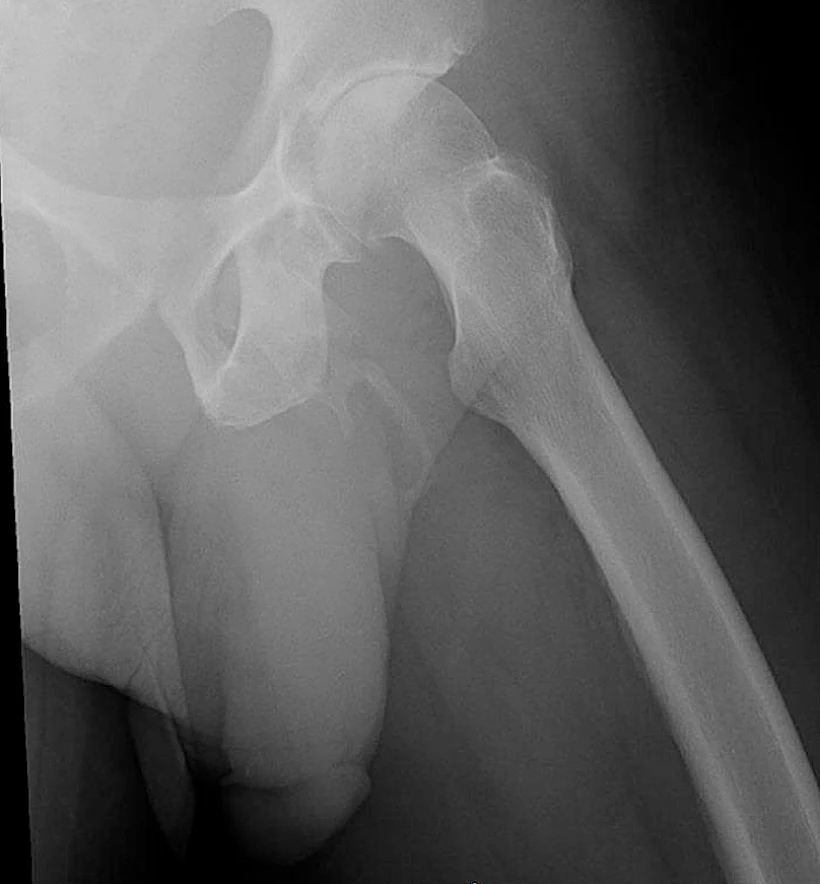

גבר בן 63 מניו יורק אושפז עם כאבים בירך בעקבות נפילה. הוא ציפה לטיפול שגרתי, אך דבר לא הכין אותו לאבחנה המטרידה שקיבלו רופאיו לאחר שבחנו את צילום הרנטגן של האגן שלו.

הרופאים ביקשו לבחון אם ישנם סימנים לשבר באגן בעקבות הנפילה, אך מה שהם מצאו היה מטריד יותר - הסתיידות דמוית עצם באיבר המין של המטופל.

ההסתיידות הזו היא תוצאה של מלחי סידן שהצטברו ברקמה הרכה של איבר המין והתקשו לכדי יציקה לאורך כל ציר הפין. הדו"ח הרפואי ציין כי המטופל לא הראה תסמינים אחרים כגון נפיחות או הפרשות.